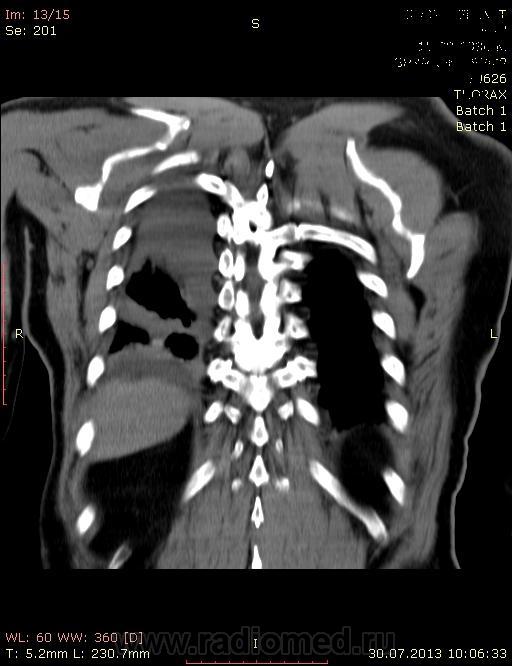

кт грудной клетки

Нужна помощь.Больной 77 лет госпит-н в хир отд. с диагнозом ЖКБ.Больному стало хуже стали беспокоять одышк. чувство нехватка воздуха.

Внезапно возникшая одышка в послеоперационном периоде всегда подозрительна на ТЭЛА плюс треугольная тень на рентгенограмме с ровными, четкими контурами. Надо искать эмболы в легочных артериях (кстати, оптимальная отсрочка после введения контраста - 20сек). Ясно также, что синдром средней доли тут никаким боком.

Предположительно: ТЭЛА. Данные полного КТ-исследования с внутривенным болюсным контрастированием помогли бы в диагностике.

КТ тут и с контрастом есть, только легочные артерии не показаны.

Уважаемый, Андрей Юрьевич! Представлены несколько КТ-изображений, среди которых два с не вполне внятным контрастированием. Разве этого достаточно для диагностики ТЭЛА? Или есть Дайком-формат, которого у меня нет?

До операций не дошли , готовили на операцию.Терапевты слушают хрипы справа.Инфильтративная тень контрастировалось с плотностью 123 ед.Н. При пневмоний  контрастируется?